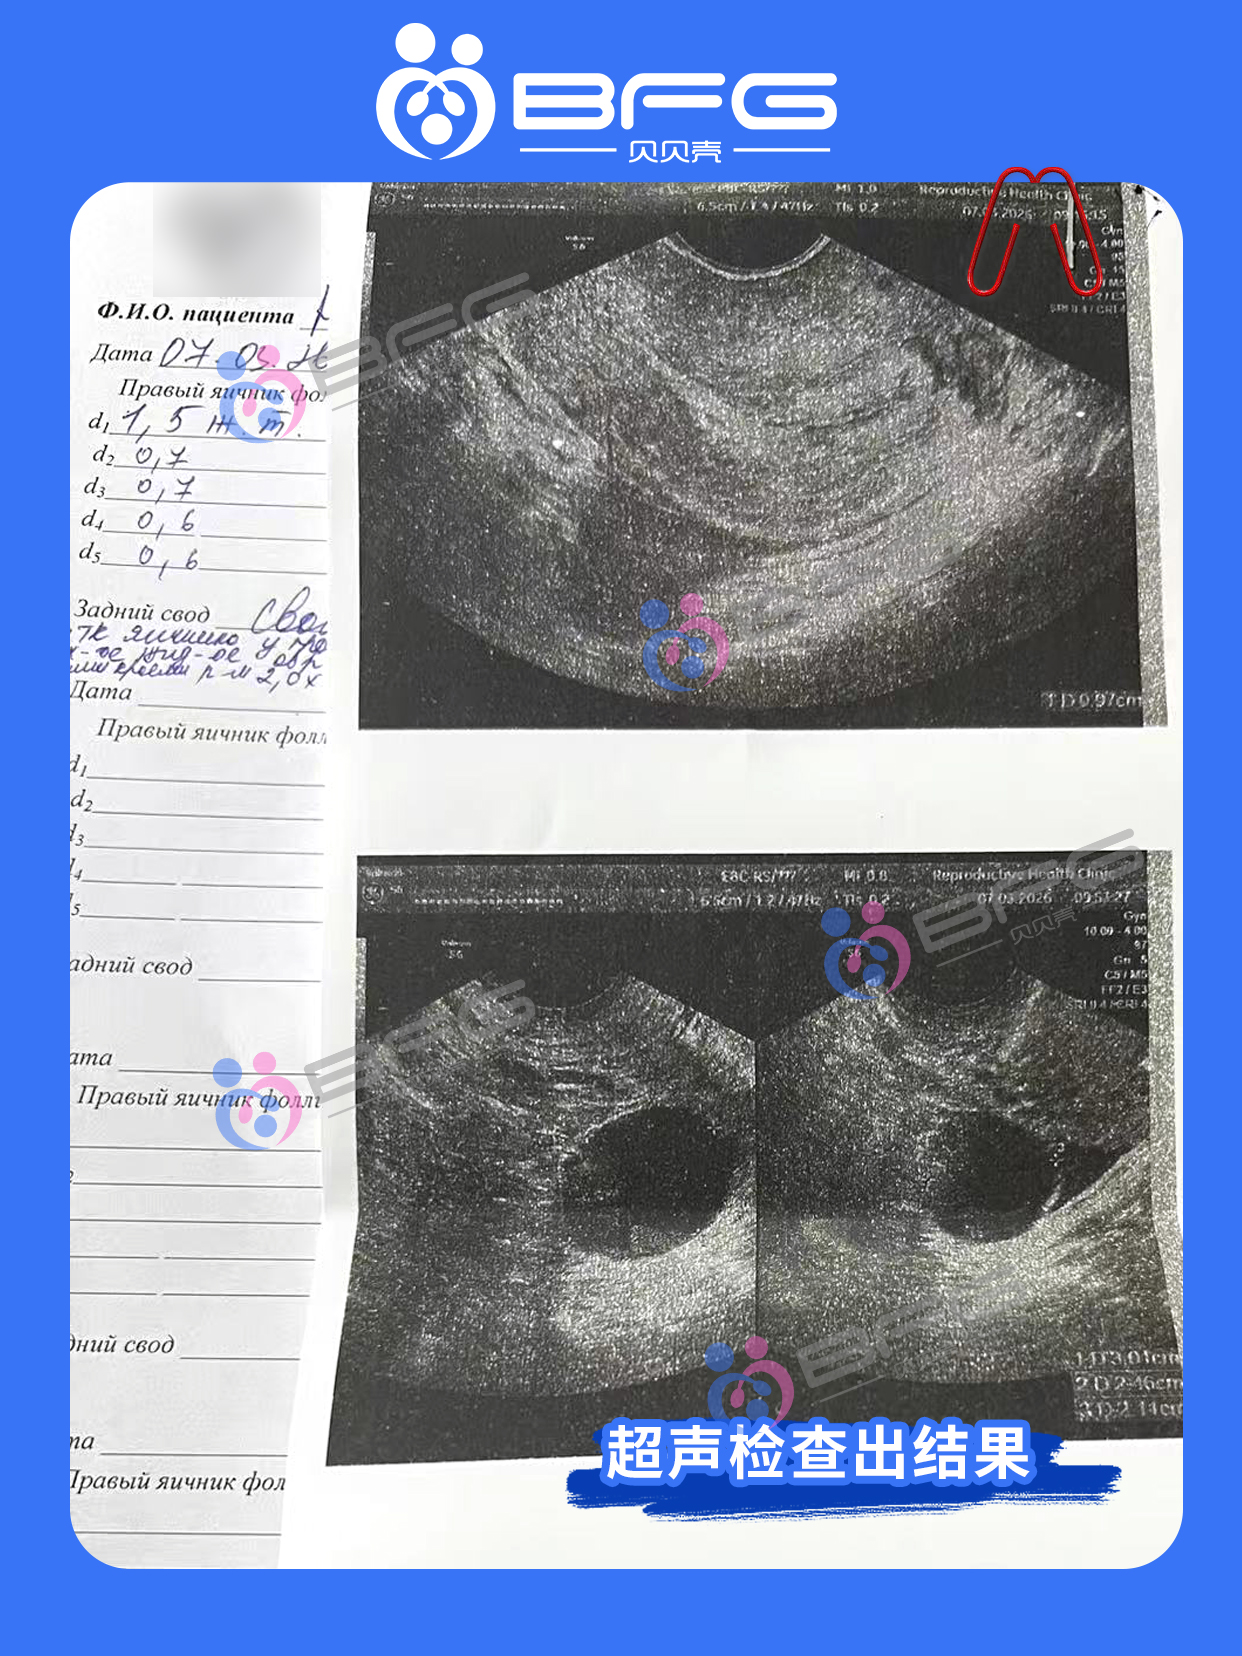

内分泌科,生殖科,妇科多学科会诊为❤妈妈评估完成,检查达标!好孕在即,专业护航每一步,静待好孕佳音。